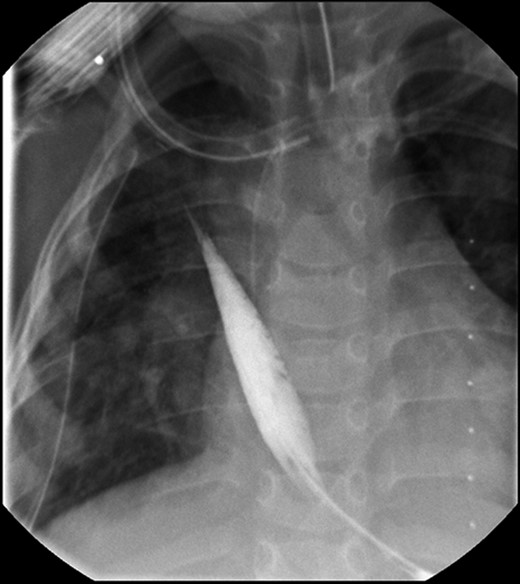

A fundoplication was performed during a subsequent hospital stay (postoperative day 237) for reflux. There was also concern for metaplasia of her distal esophagus from stratified squamous epithelium to simple columnar epithelium with goblet cells consistent with Barrett's esophagus. Her total follow-up to date has been 1377 days with her last endoscopy was performed on postoperative day 1159 from Stage 1 of her Foker procedure (Fig. 4).

Her last follow-up EGD demonstrating a patent native esophagus.